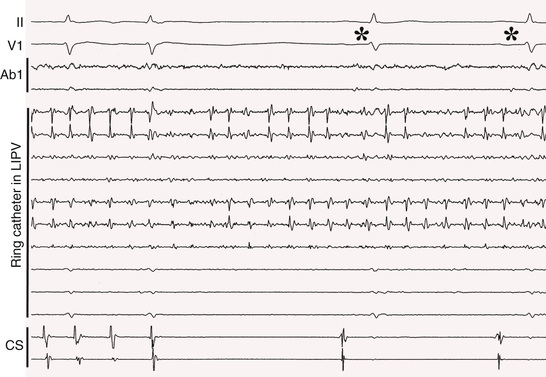

Because of their important role in triggering and maintaining episodes of AF, almost all ablation strategies include electrical isolation of the PVs (Fig. 38.8). This is often sufficient for patients with paroxysmal AF and sometimes sufficient for patients with persistent AF. Pulmonary vein (PV) isolation can be accomplished by either ostial ablation or wide-area ablation 1 to 2 cm away from the ostia, in the antral regions of the PVs. Most of the available data indicate that wide-area ablation is more effective than ostial ablation, probably because it also targets drivers that are in the antrum, outside the PV itself.43 Triggers of AF can also arise from other thoracic veins, such as the superior vena cava, coronary sinus, and the vein of Marshall. After the PVs have been isolated, infusion of isoproterenol is helpful to determine whether any non–PV triggers are present.

A variety of ablation strategies have been used for persistent AF after the PVs have been isolated: linear ablation across the left atrial roof, mitral isthmus, or cavotricuspid isthmus; ablation of complex fractionated atrial electrograms (CFAEs) in the left atrium, coronary sinus, or right atrium; various combinations of linear and CFAE ablation; and ablation of ganglionated plexi.43 The endpoint of catheter ablation of persistent AF is either completion of a prespecified lesion set (in which case sinus rhythm is restored by cardioversion) or stepwise ablation until the AF converts to sinus rhythm. Recent randomized studies have demonstrated that antral PV isolation is as effective as PV isolation plus linear ablation and/or ablation of CFAEs.44,45